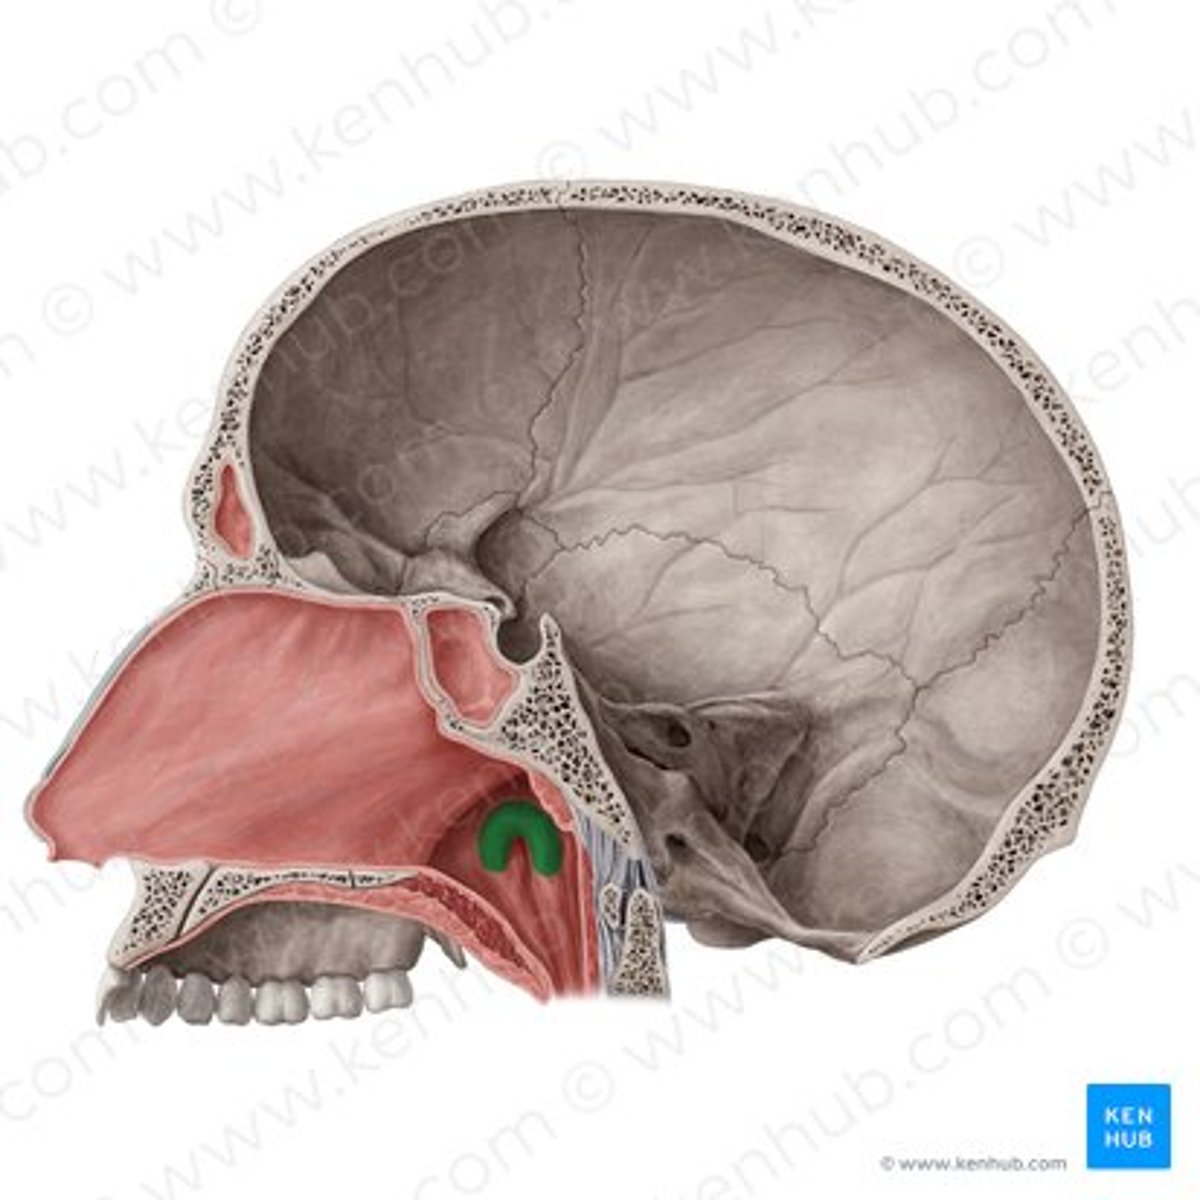

pharyngeal tonsil

tonus tubaris

opening of pharyngotympanic tube

salpingopharyngeal fold